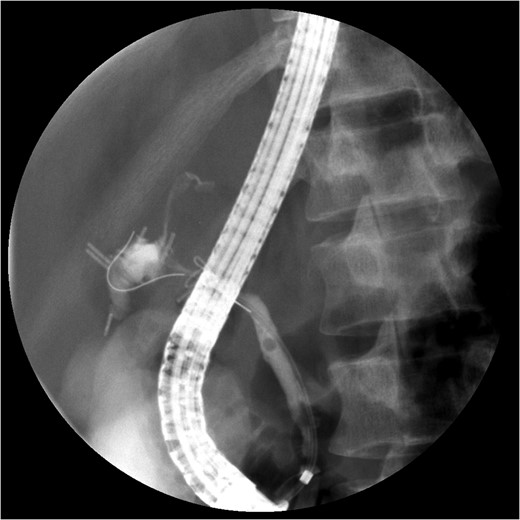

A computed tomography (CT) angiogram of the abdomen was significant for multifocal pneumonia and free peritoneal fluid. Chest CT was negative for pulmonary embolism (Figs 1, 2). Repeat ERCP confirmed a wide-open distal common bile duct at the level of multiple surgical clips with inability to pass a wire distally (Fig. 3). Interventional radiology was consulted to obtain a percutaneous transhepatic cholangiography (PTC) prior to definitive surgical repair.

ERCP with contrast extravasation from distal common bile duct. Note several surgical clips adjacent to the injury.

The PTC study confirmed the presence of a completely transected duct, and, fortunately, the ductal injury was traversed with a wire with entry into the distal ductal orifice and into the duodenum (Figs 4–6). Following the procedure, the patient was taken directly to the operating room for open surgical repair.